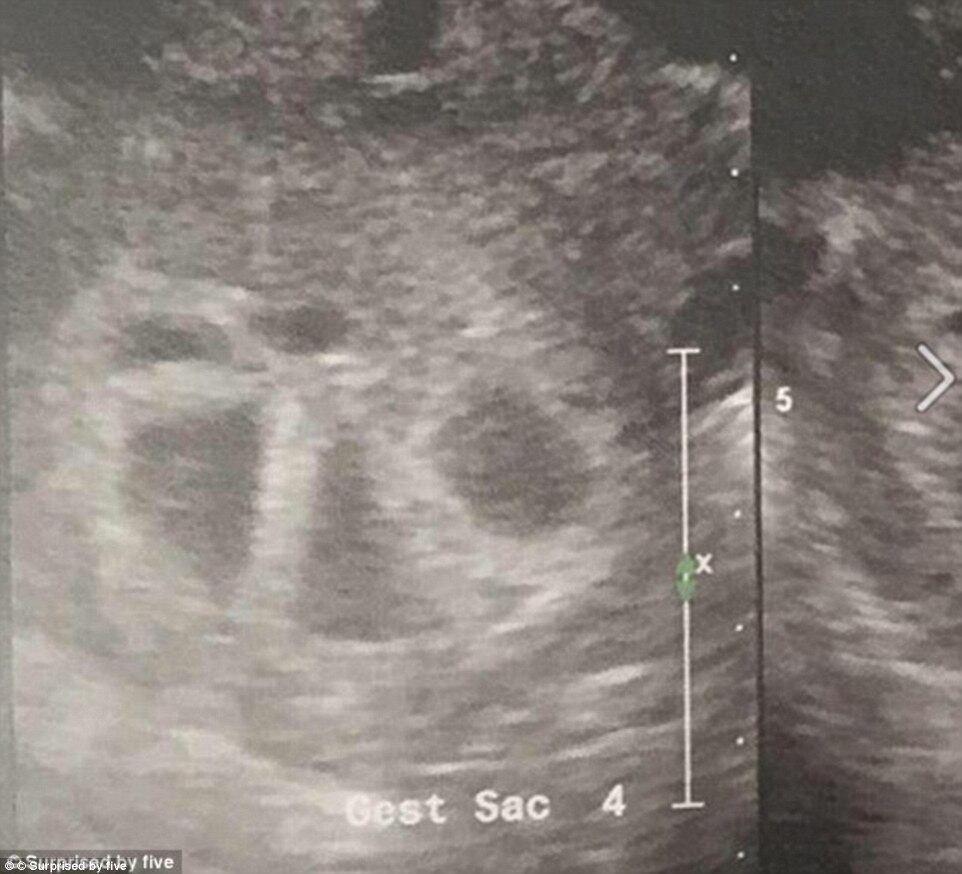

Doze idas ao banheiro em apenas uma noite, dores constantes nas costas e 6.000 calorias por dia ingeridas. Essa é a realidade cotidiana da australiana Kim Tucci, de 26 anos, que vai dar à luz a quíntuplos daqui a menos de dois meses. As informações são...

Doze idas ao banheiro em apenas uma noite, dores constantes nas costas e 6.000 calorias por dia ingeridas. Essa é a realidade cotidiana da australiana Kim Tucci, de 26 anos, que vai dar à luz a quíntuplos daqui a menos de dois meses. As informações são do portal de notícias britânico Daily Mail